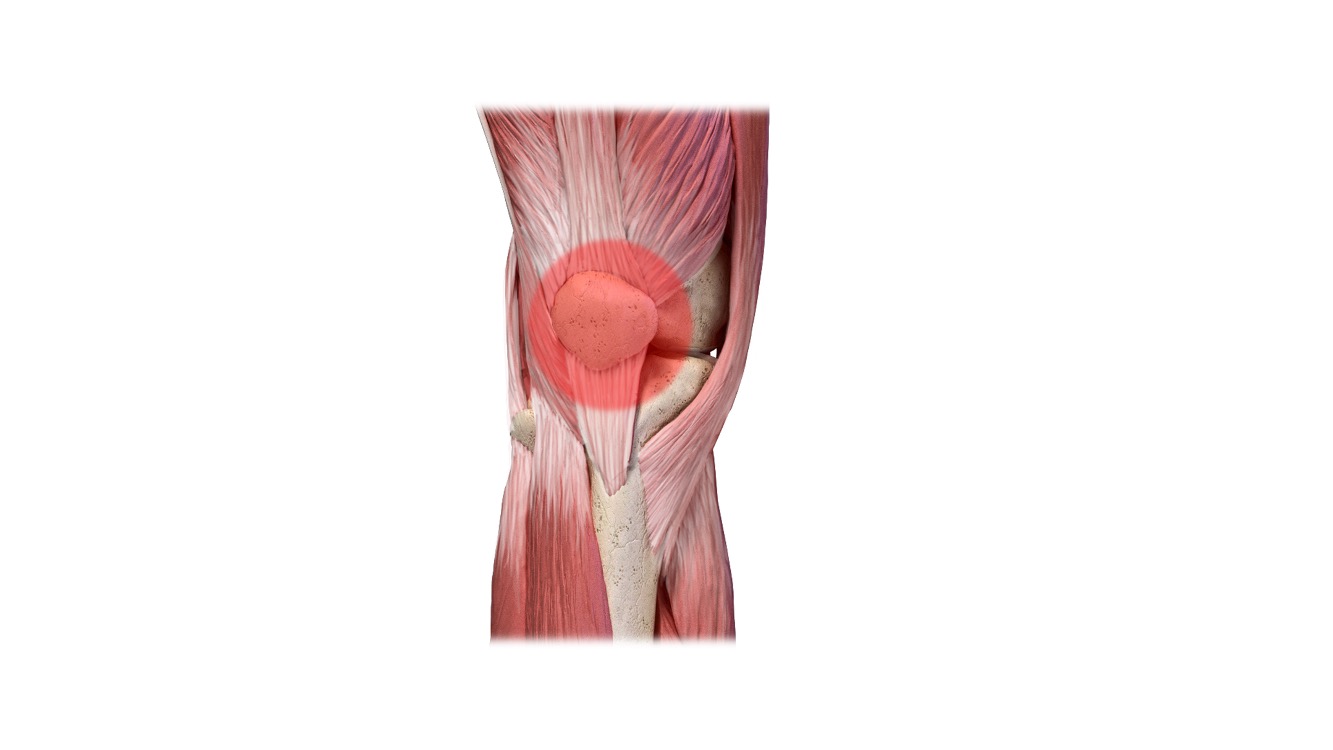

"ברך רצים"

Runner's Knee

או בשמה הנוסף, תסמונת הכאב בקדמת הברך (תסמונת פיקה-ירך). מדובר בתסמונת שמתאפיינת בכאב בקדמת הברך סביב הפיקה. כאב זה יופיע לרוב ללא סיפור של חבלה ויכול להחמיר באופן איטי או מהיר עד הגבלה משמעותית בפעילות גופנית ואף בפעילות יום יומית. עיקר הכאב מדווח לרוב במאמצים הכרוכים בביצוע תרגילים בכיפוף עמוק של הברך, ישיבה ממושכת, עליית וירידת מדרגות, קפיצה וריצה.

במסגרת תהליך האבחון יש לשלול אבחנות אפשריות אחרות לכאב במיקום זה. הטיפול מבוסס על שינוי דפוס פעילות זמני, פיזיותרפיה מותאמת, התייחסות לבעיות מבניות ברגליים, שיפור טכניקה בביצוע הפעילות הגופנית, עבודה על שליטה שרירית, אימון שיקומי וחזרה הדרגתית לריצה.

לסקירה מפורטת על פציעה זו, הכנסו לקישור הבא: